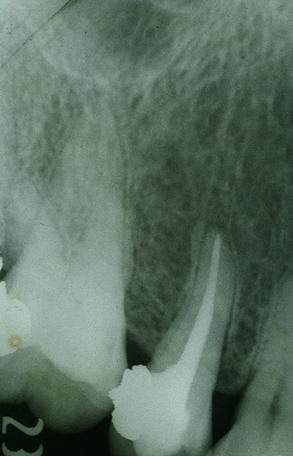

論文は、自分自身が行った歯科治療(歯内療法)の結果を、2〜3年にわたって追跡調査し、多変量解析による統計分析を行ったもので、当時としては世界でも3人しか論文を発表していない。 いずれも、私個人の単独名(単著)だが、主任教授(故・永澤恒)との連名で、米国歯内療法学会で、2度(ロサンゼルス、フロリダ)にわたって口頭発表している。